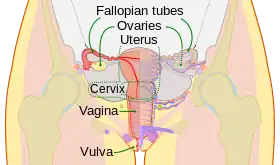

Diagram of the female human reproductive tract and ovaries | |